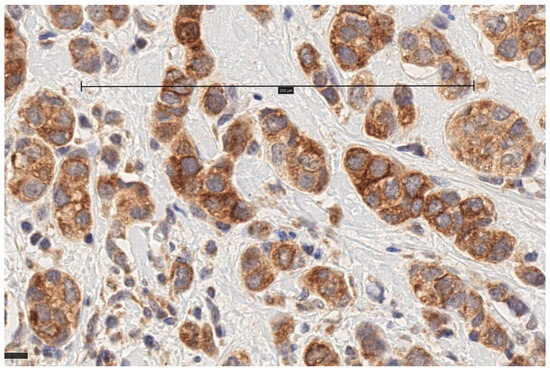

3.1. MT1 Receptor Expression